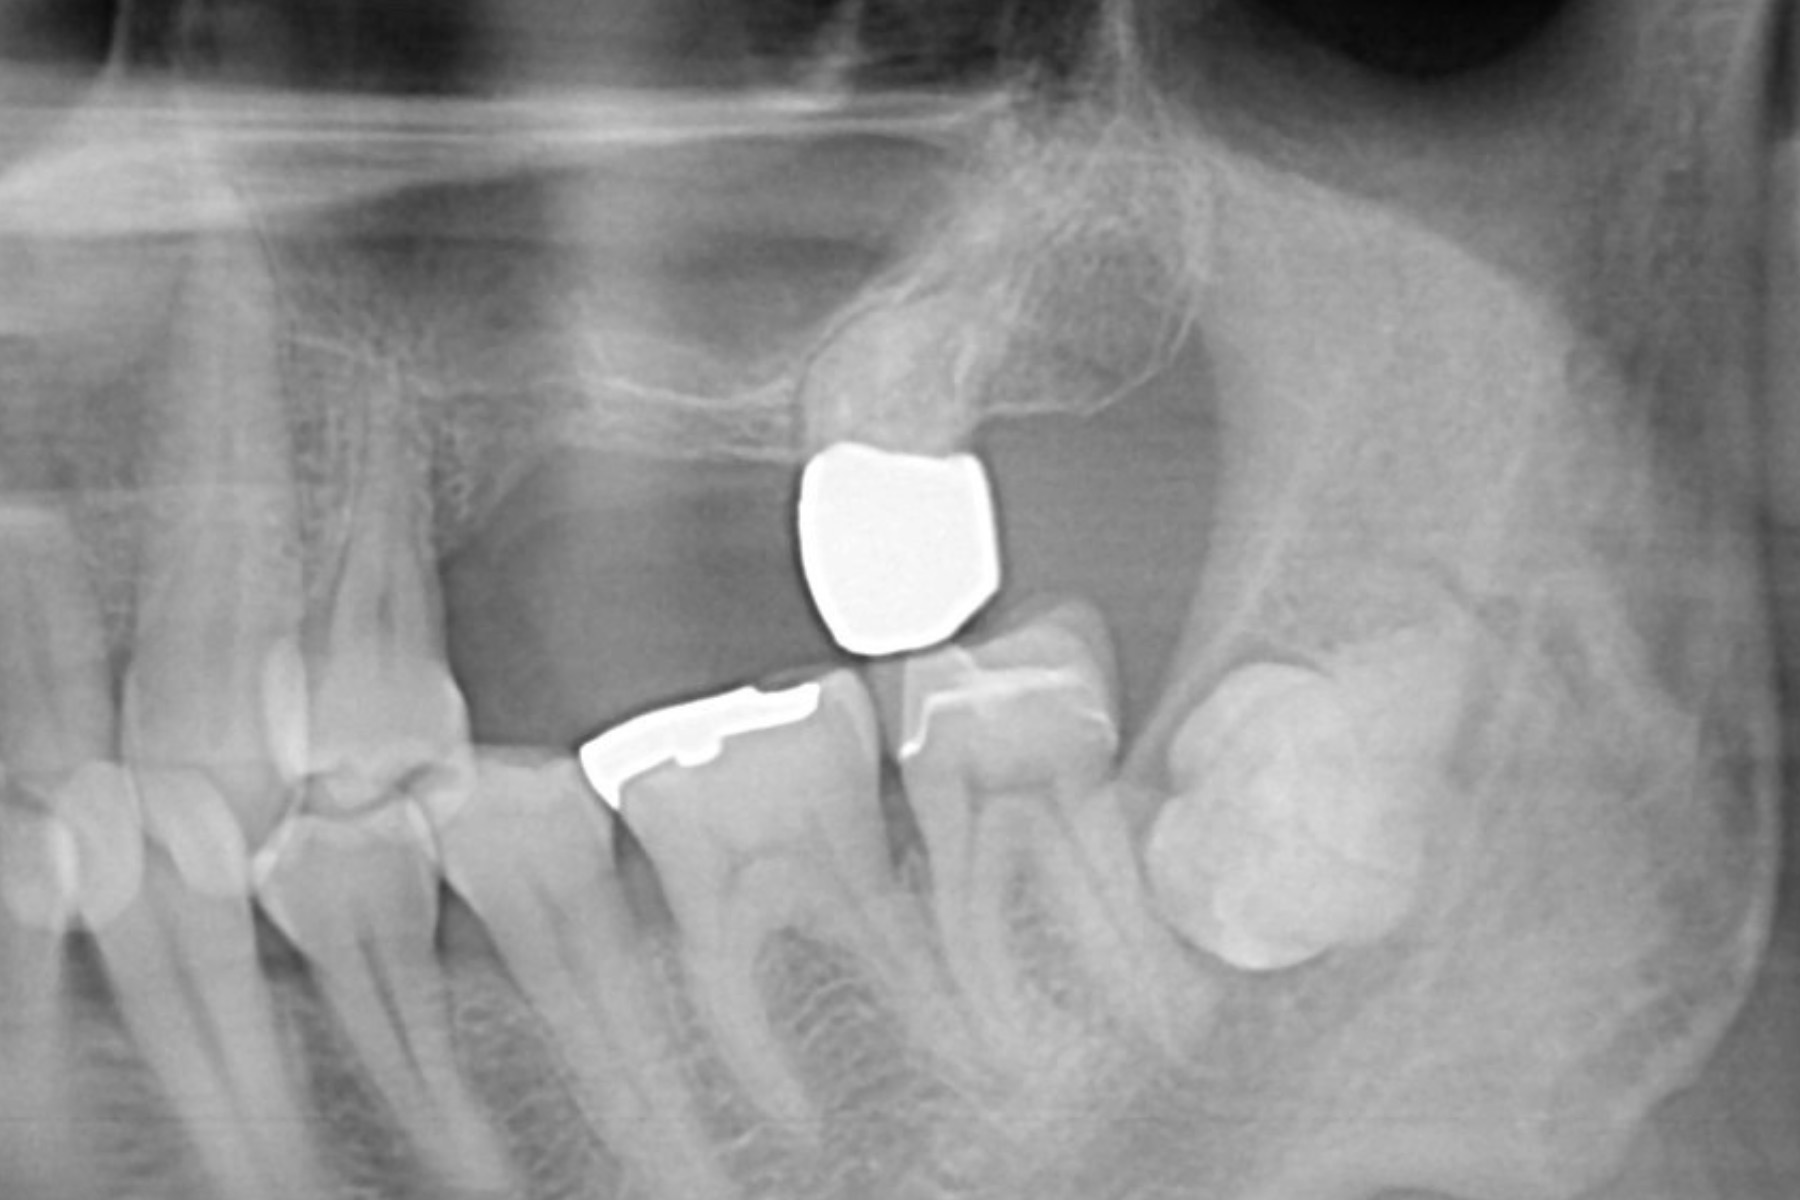

implant-case03-bf1